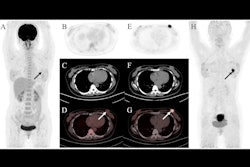

A: F-18 FAPI-04 PET/CT and CT images of a patient with locally advanced esophageal squamous cell carcinoma (LA-ESCC) with an outcome classified as partial response. B: F-18 FAPI-04 PET/CT and CT images of an LA-ESCC patient with an outcome classified as stable disease. Images courtesy of the Journal of Nuclear Medicine."The ability to identify patients with a poor prognosis in advance via imaging will help to realize individualized treatment of tumors," wrote corresponding author Dr. Shuanghu Yuan, PhD.

The researchers evaluated standard uptake (SUV) values based on tumor uptake of the F-18 FAPI-04 radiotracer, as well as target-to-background ratios (TBR) between the groups. At baseline, quantitative measures of patient response were significantly higher in those patients who did not respond to treatment compared to those who did -- specifically TBRblood (12.53 vs. 10.29), TBRmuscle (12.24 vs. 9.81), and SUVmean (14.30 vs. 4.25), Yuan's group reported.

In addition, the investigators used receiver operating characteristic (ROC) curve analysis to evaluate the accuracy of these parameters for predicting patient chemoradiotherapy response. The TBRblood measure showed an area under the curve (AUC) of 0.88, while TBRmuscle showed an AUC of 0.89 and SUVmean an AUC of 0.87, the researchers found.